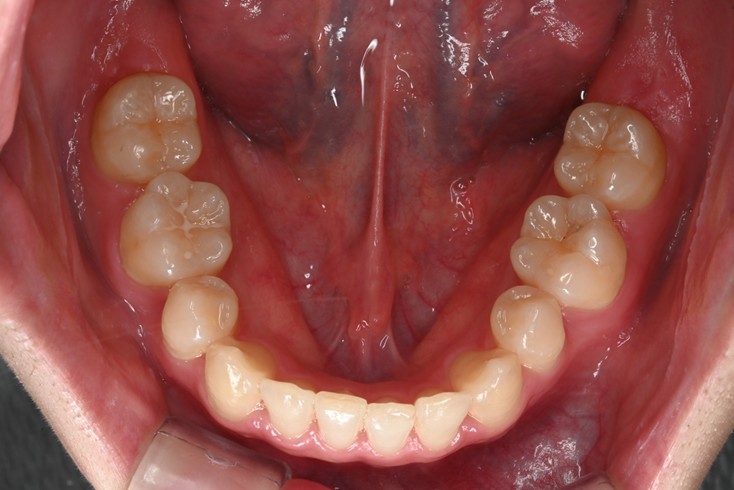

症例2:八重歯が気になる

| 患者様データ | 20代 女性 |

| 来院主訴 | 八重歯が気になる。 |

| 治療内容 | 八重歯を治すために上の親知らずを抜歯し、インビザラインにてマウスピース矯正を開始しました。かみ合わせを整えるためにゴムかけを行いました。 |

| 概算治療費 | 約85万円 |

| 治療期間 | 1年3ヶ月 |

| 通院回数 | 8回 |